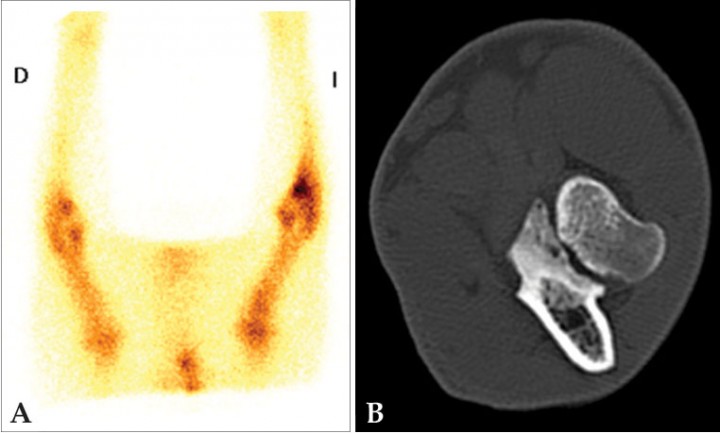

Figura 11

Estudio de un paciente canino con dolor inespecífico en extremidad anterior izquierda. (A) Gammagrafía ósea, adquisición en fase ósea 2 horas después de la administración de 99mTc-HDP, proyección ventral de las extremidades anteriores en las que se observa un foco con aumento de captación del radioisótopo en la región de la articulación del codo izquierdo, principalmente en la porción distal de la misma. La imagen es compatible con patología del proceso coronoides medial. (B) TC del codo izquierdo del mismo paciente, plano transversal en algoritmo hueso en el que se observa un área hipoatenuante en el coronoides medial sin línea de fractura evidente, compatible con condromalacia y enfermedad de coronoides medial sin presencia de fragmentos. La gammagrafía permitió en este caso localizar la articulación con patología (codo) que es la que se examinó con la TC.

Figura 12

Estudio por imagen de un perro con cojera de la extremidad anterior izquierda. (A) Gammagrafía en fase ósea en la que se aprecia aumento de captación de 99mTc-HDP en la articulación escapulohumeral. (B) Reconstrucción sagital de TC de hombro izquierdo en algoritmo hueso con pequeños defectos subcondrales en la superficie caudal de la cabeza humeral compatible con osteocondrosis (TC cortesía de ARS Veterinaria). La gammagrafía permitió en este perro de raza grande (montaña del Pirineo) localizar la articulación que presentaba patología para realizar la TC solo de la región anatómica afectada.